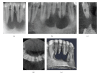

Cone Beam Computed Tomography (CBCT) is a diagnostic imaging modality that provides high-quality, accurate three-dimensional (3D) representations of the osseous elements of the maxillofacial skeleton. CBCT systems are available that provide small field of view images at low dose with sufficient spatial resolution for applications in endodontic diagnosis, treatment guidance, and posttreatment evaluation. This article provides a literature review and pictorial demonstration of CBCT as an imaging adjunct for endodontics.